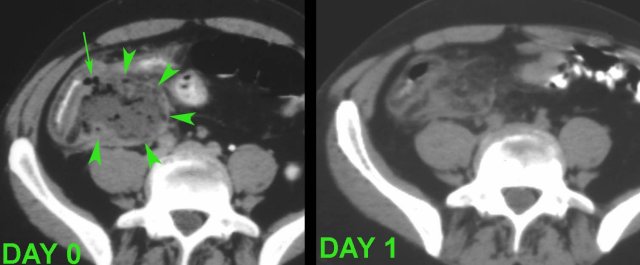

Some patients with an “appendiceal abscess” are better off with immediate surgery.

These two patients were both ill with a high CRP and signs of generalized peritonitis.

US and CT confirmed paralytic ileus and large, not-well walled-off air-fluid collections, and in the right patient some free air (arrows).

These combined clinical and CT findings indicate a failing defense mechanism, warranting surgery.